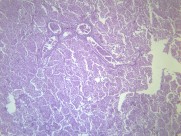

大叶性肺炎(lobarpneumonia)主要是由肺炎链球菌引起,病变累及一个肺段以上肺组织,以肺泡内弥漫性纤维素渗出为主的急性炎症。病变起始于局部肺泡,并迅速蔓延至一个肺段或整个大叶。临床上起病急骤,常以高热、恶寒开始,继而出现胸痛、咳嗽、咳铁锈色痰,呼吸困难,并有肺实变体征及外周血白细胞计数增高等。病程大约一周,体温骤降,症状消失。该病多发生于青壮年男性。疾病常见诱因有受凉、劳累或淋雨等。属于中医“风温”、“肺痈”等范畴。